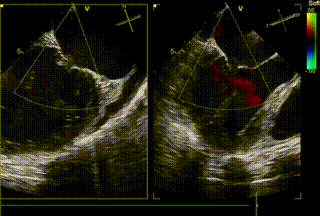

患者全麻后,在经食道超声心动图和X射线引导下,经股静脉入路,将申淇淇麟®系统瓣膜夹顺利送至二尖瓣A2/P2区域,经调整位置使瓣膜夹垂直对合缘,跨瓣。由于后瓣长度较短,很难同时捕获,遂应用单瓣叶独立捕获功能,成功地分别捕捉二尖瓣前叶和后叶,经超声心动图反复确认瓣叶夹持牢固,反流量减少,跨瓣压差4.3mmHg。遂释放瓣膜夹,超声心动图评估瓣膜夹位置和功能良好,瓣膜夹活动度低,手术顺利完成。

术后4天TTE显示反流减轻,瓣膜夹稳定